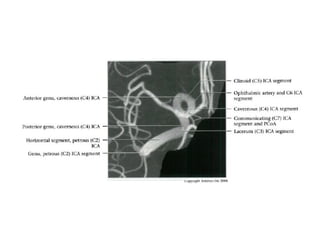

Overview

• Complex course with several vertical /

horizontal segments, 3 genus (one

petrous, two cavernous)

• Six intracranial segments (Cervical lCA =

C1):

- Petrous (C2), Lacerum (C3),

Cavernous (C4), Clinoid (C5),

Ophthalmic (C6), Communicating (C7)